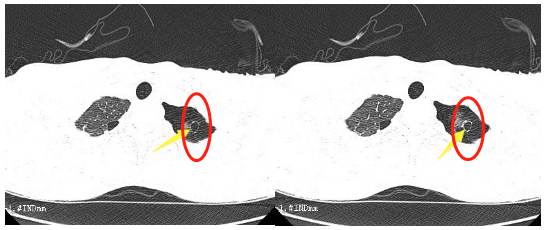

這段時間,16歲的小王突然出現了胸悶的癥狀,持續一周都不見好轉。到我院胸心外科檢查后,胸片提示左側液氣胸,積氣為主,結合患者術前CT檢查情況,考慮為肺大泡破裂引起的氣胸。

患者肺大泡明顯,術后切口較小。